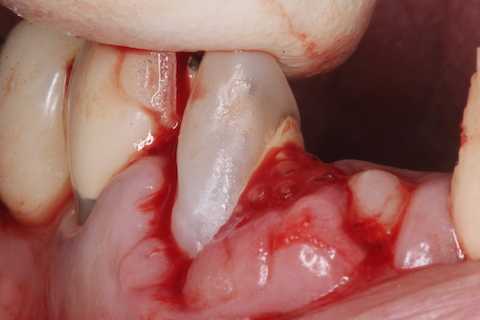

あとは接着固定しながら、歯冠を再建していく。